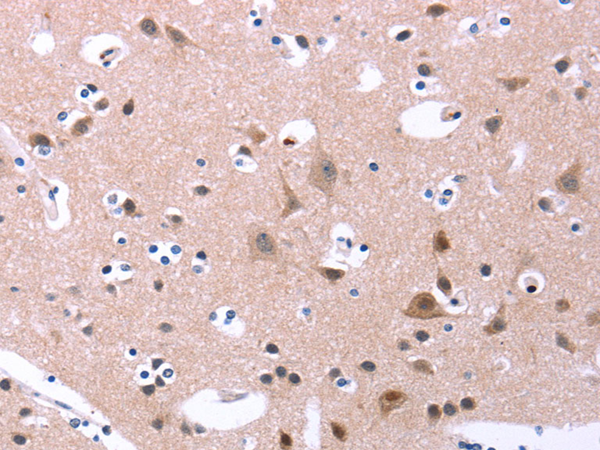

分类: 科研抗体货号: P04240别名: Fz2; fz-2; fzE2; hFz2应用: IHC反应种属: Human, Mouse, Rat